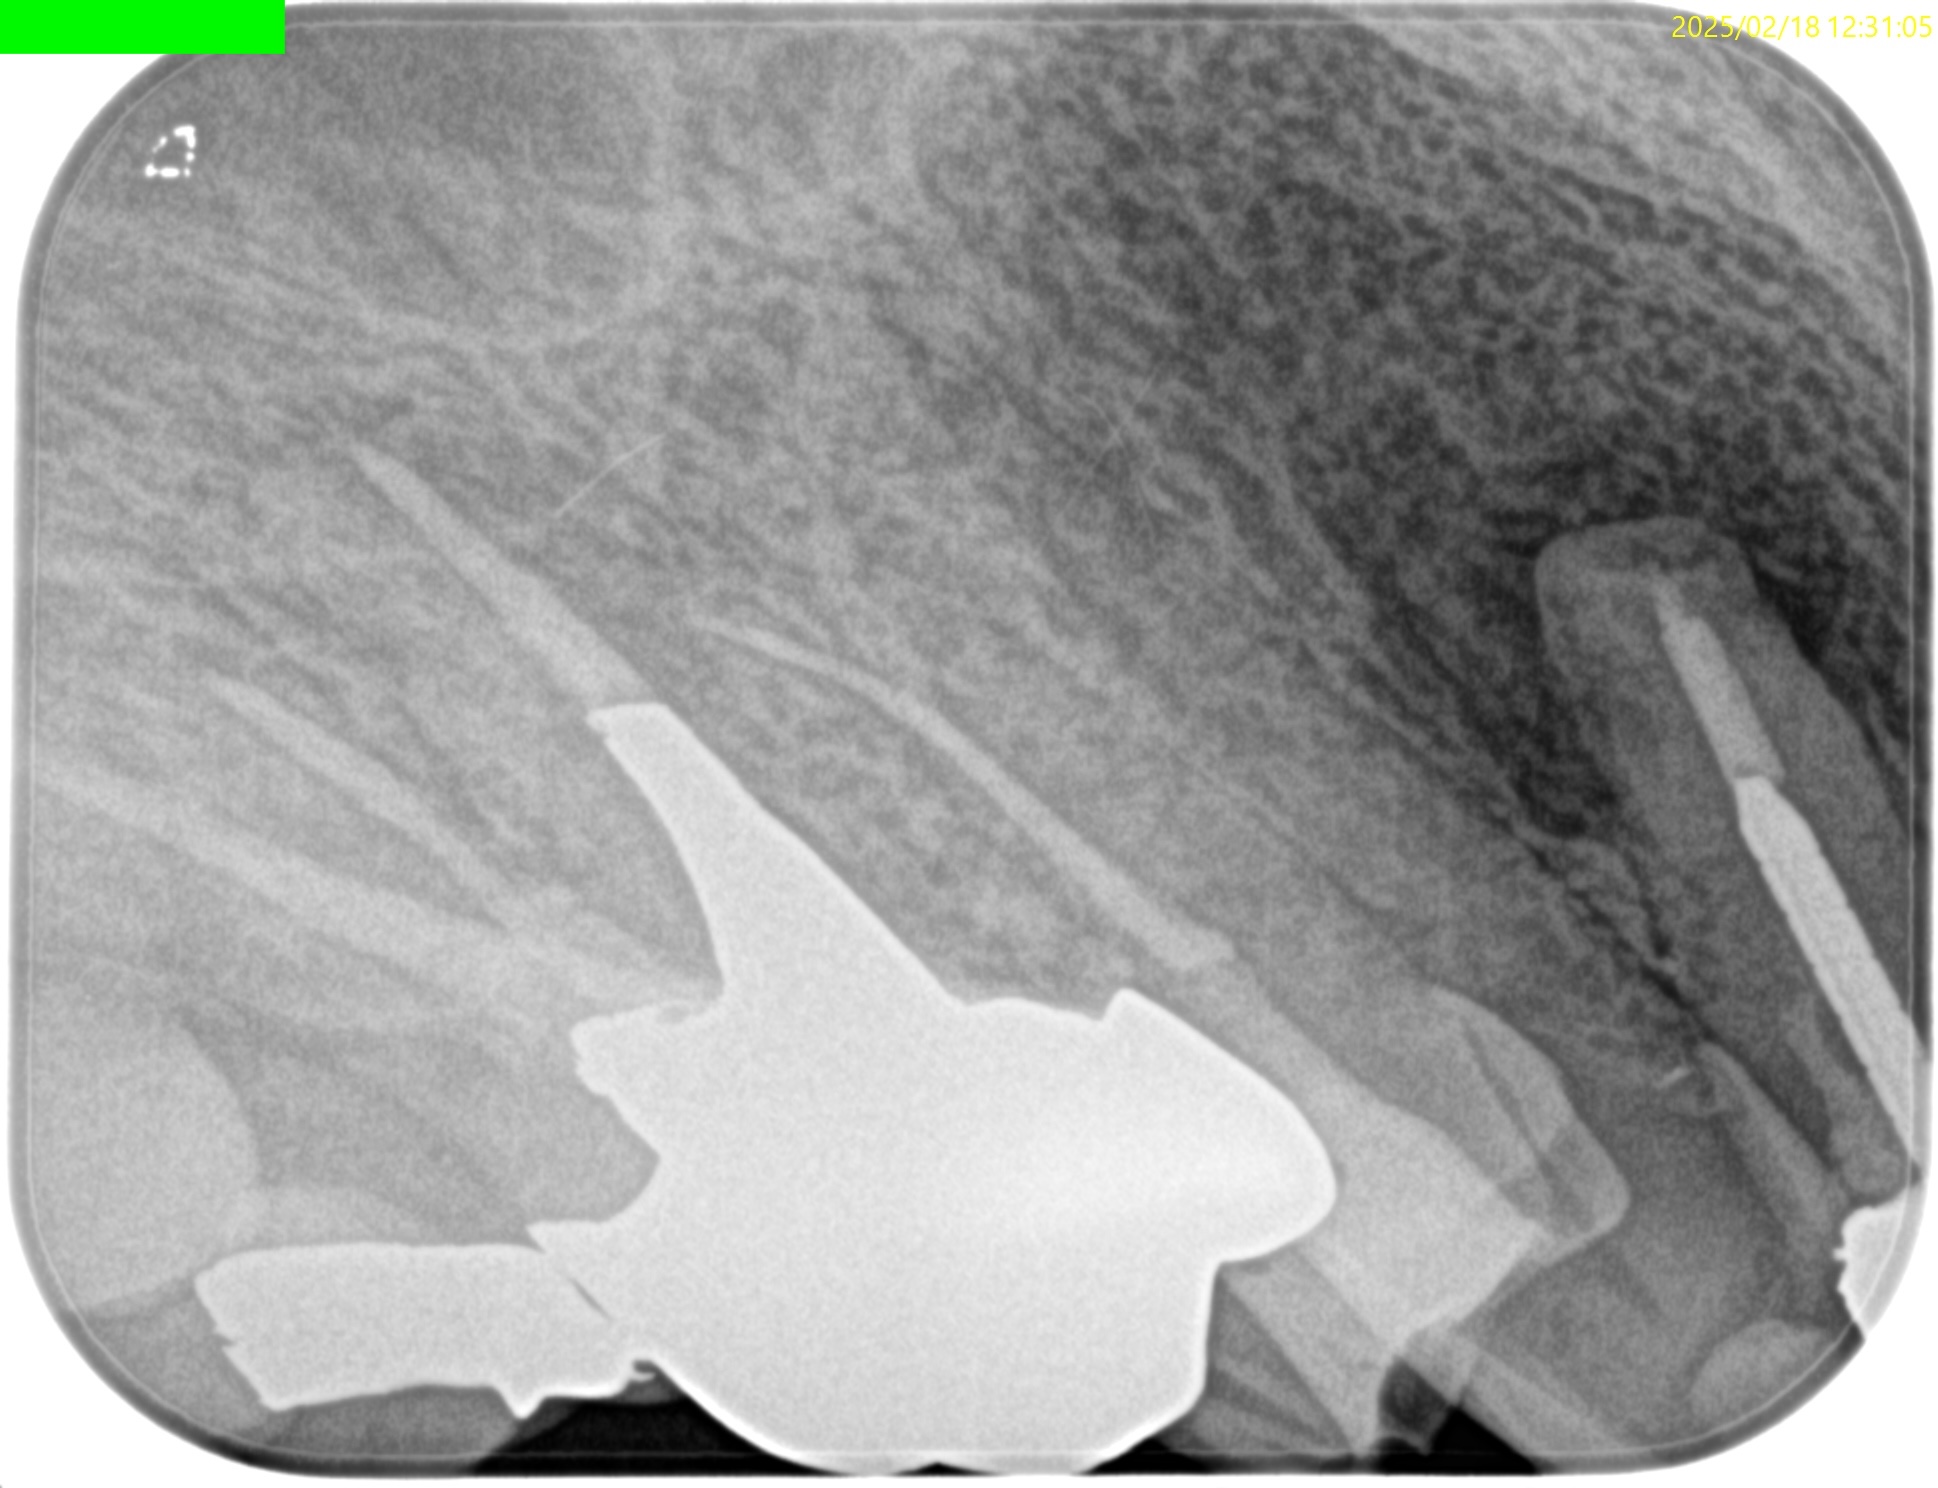

治療前の予測としては以下だ。

CEJよりも13mm先にApexがある。

が、この際にOsteotomyを行わなくてもApexには辿り着ける。

そしてApexから3mmで切断した時に、頬舌的には4.4mm削るだけで済む。

Very easyな外科治療だ。

そしてその際、Gutta PerchaがMBの中心にあることからこの根管は1根管であるということまでわかる。

まさにSuper easyなApicoectomyである。